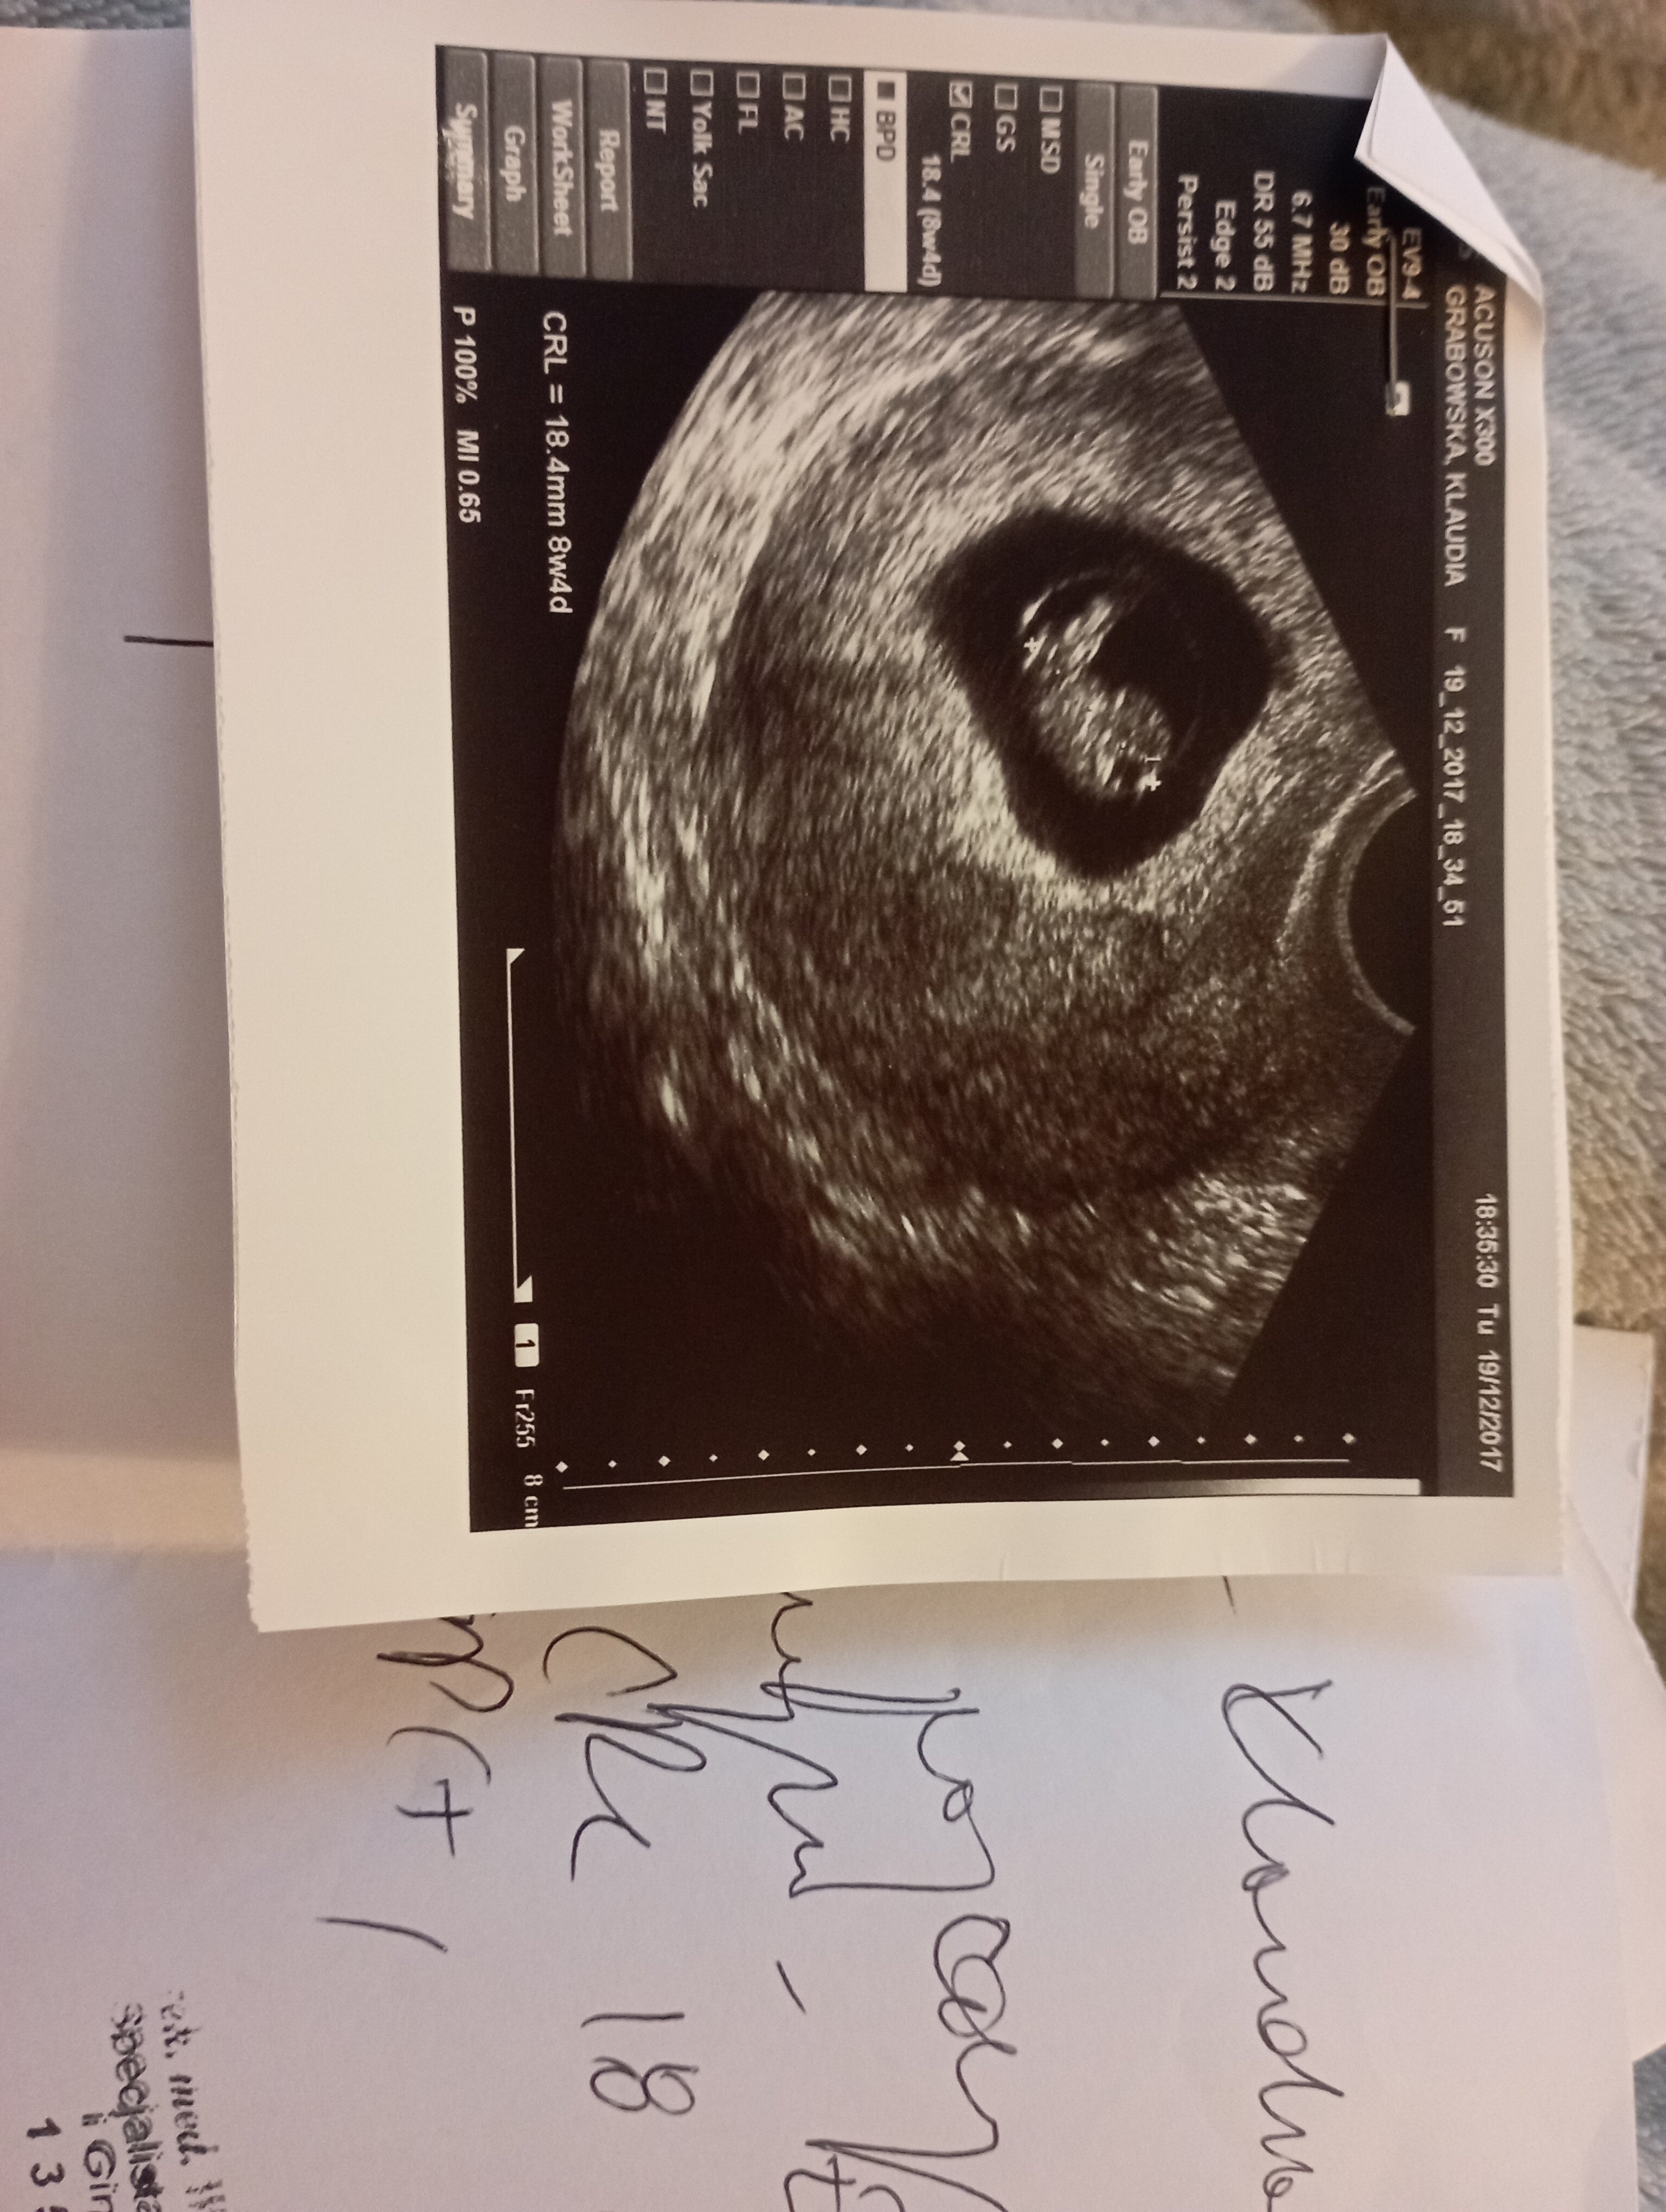

Mam pamiątkowe pudło z pierwszej ciąży i z pierwszych rzeczy córeczki. Typu , smoczki, pierwsza butelka, karuzela, pierwszy gryzak,miś, buciki w których zaczęła chodzić, pamiątki z chrztu, karta ciąży , ubranko w którym wyszła ze szpitala, pępowinę i takie tam różne. I tak właśnie przeglądam zdjęcia z USG. I mam zdjęcie z 8 tygodnia. Już widać ładnie główkę itp.

W czwartek będę miała 6+3 ale na prywatnej wizycie po 20ym października będę 8+3 to pewnie będzie widać podobnie <3

Zobacz załącznik 1574321